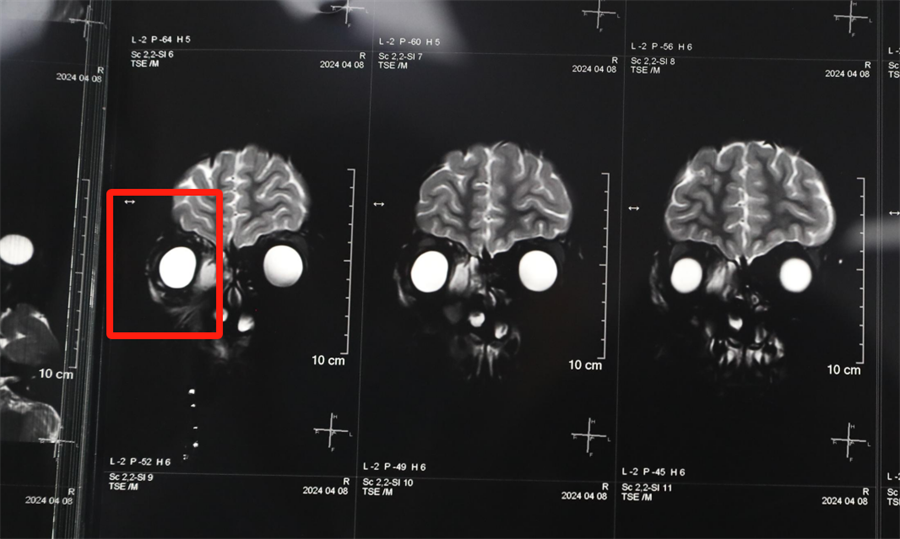

经眼科、耳鼻喉科联合会诊,医生发现孩子是因为患了急性鼻窦炎,导致右眼急性细菌感染,确诊为“右侧眶蜂窝织炎、眶内脓肿”。考虑到此病进展较快,可能导致视力下降甚至失明,耳鼻喉科立即将患儿收治入院。静脉输液、对症支持治疗、密切监测视力变化,一切有条不紊。入院第2天,孩子自觉右眼视力下降明显,眼科紧急会诊发现,其右眼视力从患病前的1.0下降到0.4。

北京儿童医院常驻专家、蜜桃视频 副院长杨小健决定立即手术治疗引流眶内脓液,并组织多学科联合会诊。考虑到患儿年龄较小,杨小健副院长决定采取内镜经鼻腔手术引流脓液,这种手术方式创伤小、恢复快、效果确切,而且避免了外切口瘢痕,不需要反复进行局部消毒换药。但是孩子鼻腔解剖结构本身就狭窄,而且处于急性感染期,术中出血风险较大,手术难度较高,对麻醉技术也有着很高的要求。

最终,杨小健副院长熟练地将手术器械通过小小的鼻孔,伸入到曾被公认为“手术禁区”的眶鼻交界区。一个多小时后,她成功地将眼眶脓肿充分引流出来。术后,医院多学科团队密切观察患儿病情变化,每日查房讨论并及时调整治疗方案。最终,通过全体医护人员的共同努力,患儿术后第3天右眼斜视就消失了,视力也恢复到了1.0。术后5天,患儿高高兴兴地出院了。